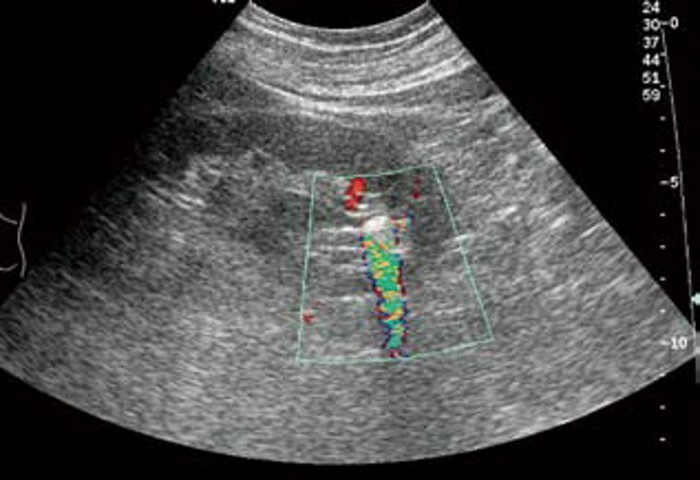

1. 肾内小结石:一般出现在肾乳头旁,表现为圆形或椭圆形的强回声斑点,周围有少量无回声区,后方可有淡声影,有的则不明显。CDFI 显示“闪烁”伪像,有助于小结石的识别。

典型病例

患者,男,12岁,因运动后多次突发腹痛,腹痛不能缓解并伴有恶心,面色苍白来院就诊,尿常规检查可见红细胞。超声检查显示:双肾大小形态大致正常,轮廓清,包膜光滑,实质回声尚均,呈低回声。右肾未见明显分离,左肾集合系统分离约1.1cm,左肾内可见0.9cm×0.7cm强回声,后方有声影。

超声提示:左肾集合系统分离,左肾结石。